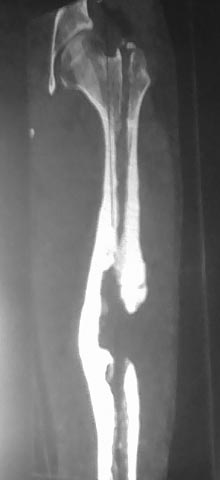

ТП, открытый оскольчатый перелом левого бедра со смещением

Наложение АВФ на левое бедро 31.03.12

*Перемонтаж АВФ на левом бедре 20.04.12

*Снятие АВФ 25.07.12

Перелом регенерата 28.07.12

-Повторное наложение АВФ.

В последующем с образованием функционирующего свища.

*1.11.12 Демонтаж АВФ с левого бедра, удаление отломка стержня

*20.11.12 БИОС левого бедренной кости

*21.06.13 Удаление стержня из левого бедра.

*8.10.13 Секвестрнекрэктомия левой бедренной кости ,коллапано-мышечная

пластика секвестральной полости

*21.01.14 Фистулосеквестрнекрэктомия левого бедра с коллапанопластикой

С января 2014 года неоднократные обострения с подъёмом температуры и

местными проявлениями (отёк, гиперемия левого бедра, обильное гнойное

отделяемое из свища). Посев Staf.epiderm MSSA –антибиотикотерапия

Амоксиклав 1.2 в\в 3 раза в день с переходом на таблетированную форму

курсами до 21 дня. Инфузионная терапия, физиолечение, баротерапия,

местное лечение- сохраняется функционирующий свищ, без тенденции к

заживлению

Ваши предложения по лечению